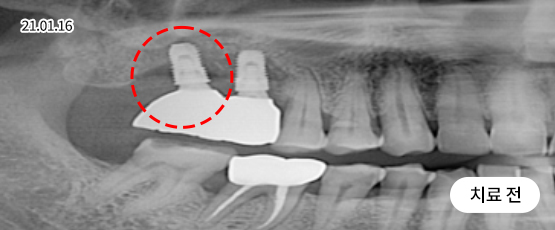

임플란트 재수술

처음보다 더 어렵고 까다로운 재수술 임플란트

잘못된 임플란트 수술과 잘못된 임플란트 관리는 부작용을 발생시킬 수 있으며, 통증을 동반하게 됩니다.

임플란트 재수술은 기존 임플란트를 제거 후 새롭게 잇몸뼈를 만들고 알맞은 잇몸형태를 잡아내어 새 임플란트를 식립하는 시술입니다.

재수술이 필요한 대상

임플란트 주위염으로 인해 잇몸뼈가 녹은 경우

임플란트를 제대로 식립하지 못한 경우

오래된 임플란트가 흔들리는 경우

임플란트가 서로 너무 가깝게 심어져 염증이 생긴 경우